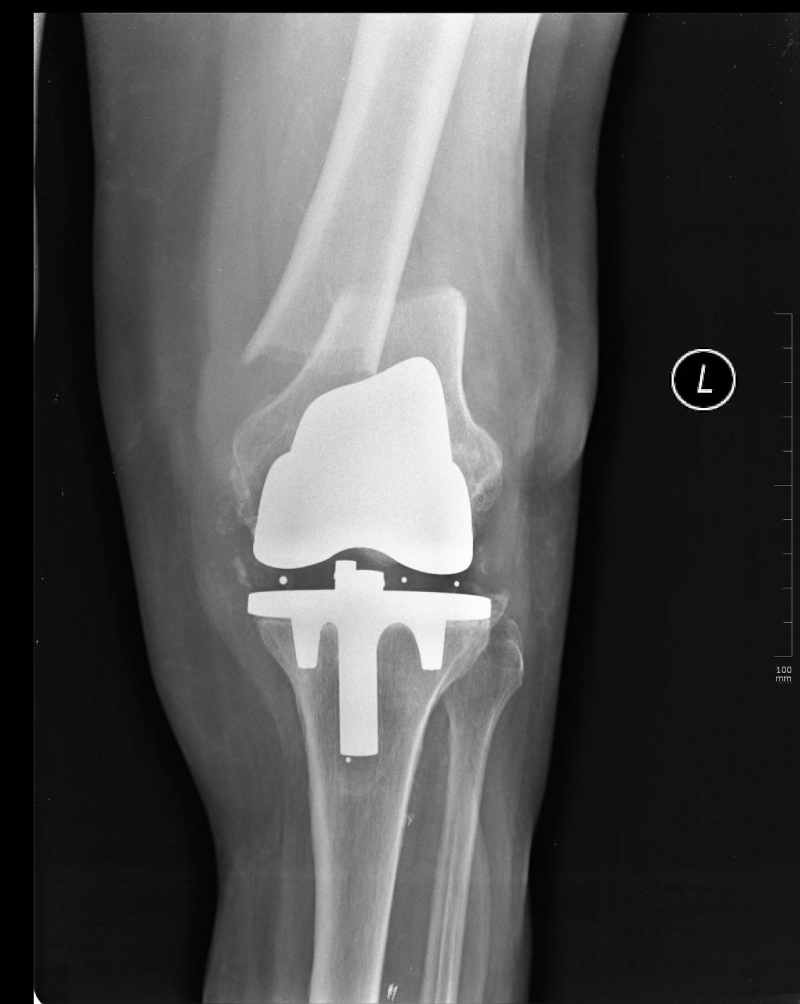

Radiographs demonstrated a fracture at the supracondylar region of the femur with significant displacement and well-functioning prosthesis (Figures 1 and 2). According to Rorabeck classification this fracture was classified as type two.8 Internal fixation was planned, however, due to multiple co-morbidities and relatively high risk of anaesthesia, a decision was made to manage the fracture by external fixation.

Figure 2: X-rays of the patient demonstrating a Rorabeck type 2 supracondylar displaced periprosthetic fracture